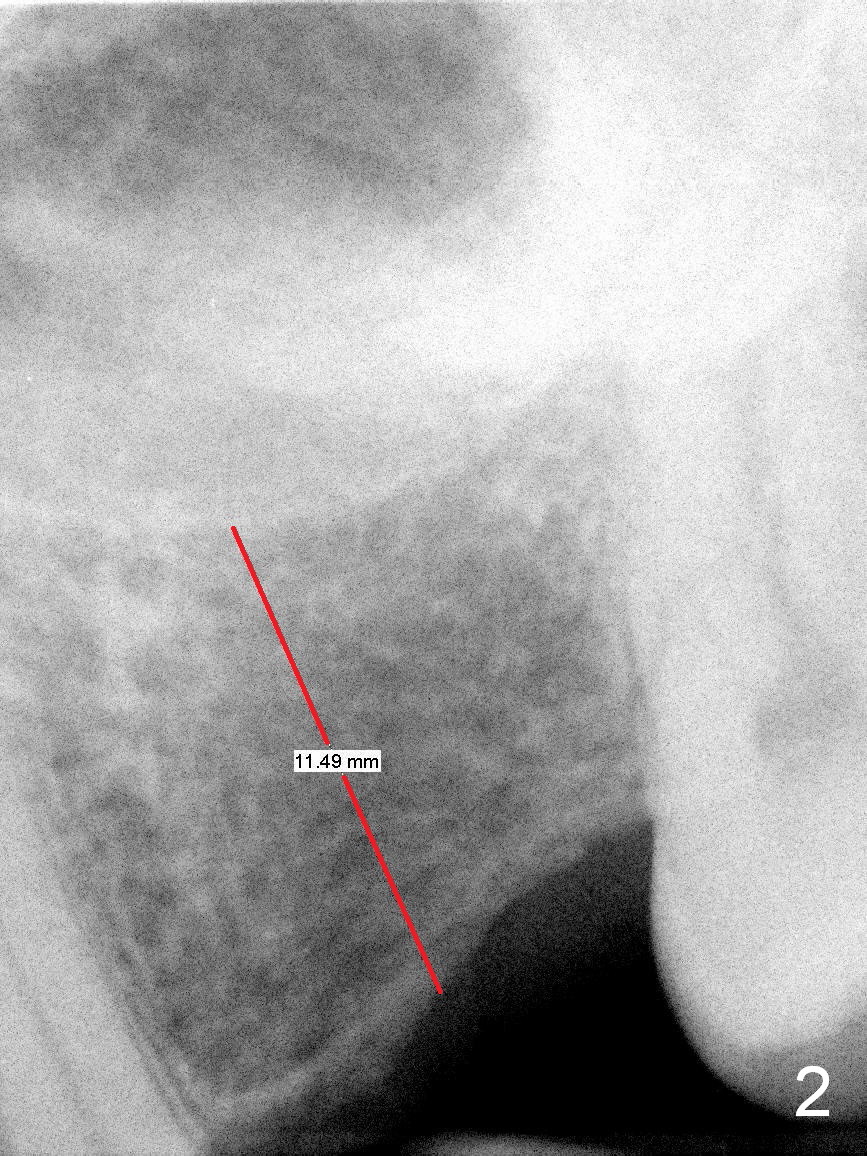

A 49-year-old man is an engineer. The tooth #14 is missing (Fig.1,2). He wonders how a one-rooted implant can replace a three-rooted tooth. Anyway, osteotomy is initiated at the site with 2.5 mm reamer in place (Fig.3). A 5x8 mm Bicon implant is placed (Fig.4). Seven and a half months later, the bone density next to the implant plateau appears to increase (Fig.5 arrowheads, as compared to Fig.4). The beauty of Bicon implant is that the crown (Fig.6 C) can be extraorally cemented to the abutment (A) prior to re-seating. Two years and 3 months post cementation, while no residual cement is visible, the bone density at the crest has increased (Fig.7 arrowheads). The crown is de-cemented 4 years 4 months post cementation; it appears that the abutment is small and short (5x2 mm 10 degree stealth). The bone density of the cortex around the implant (Fig.9 ^) is higher than that at #15 and #3.